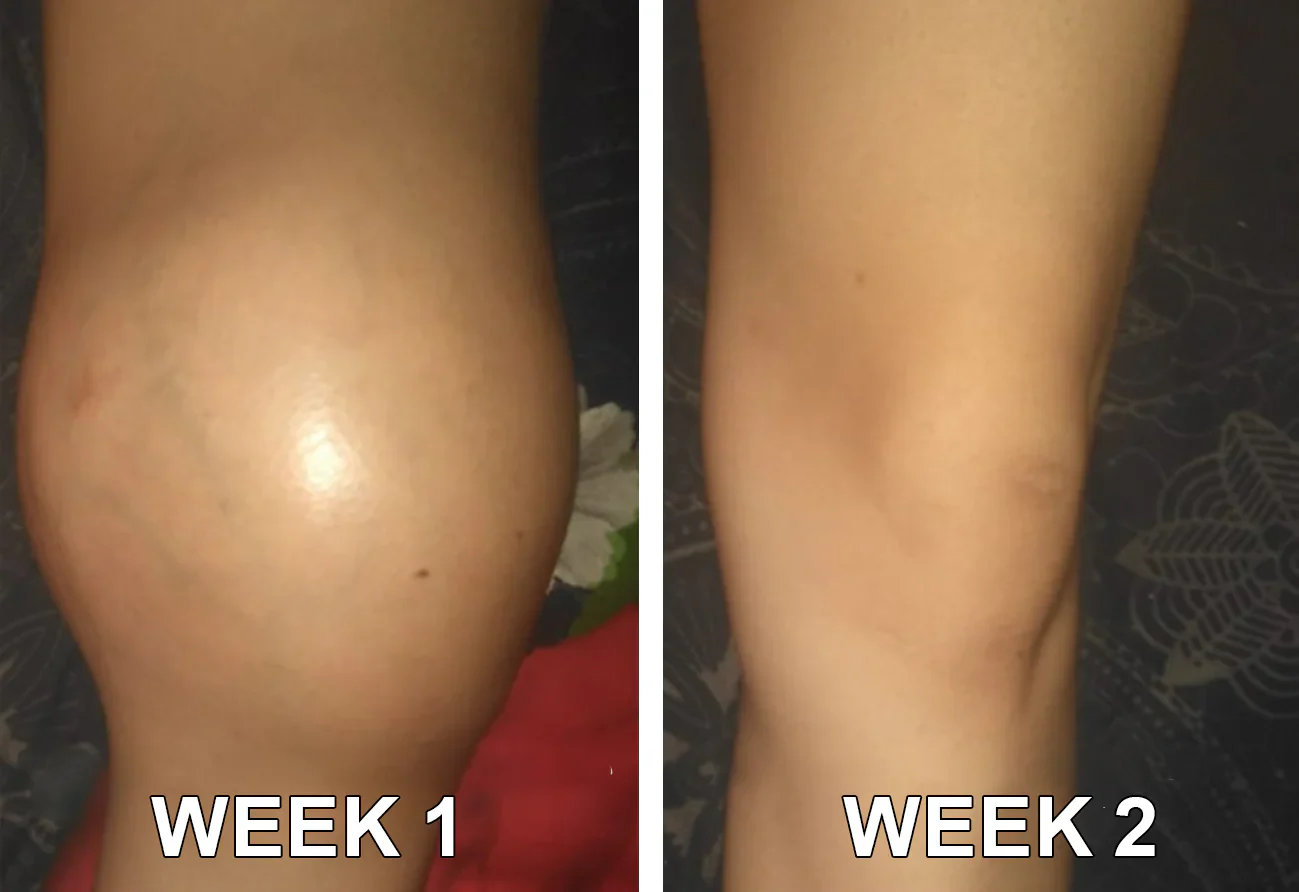

TLOPA® Botulinum Toxin és Méhméreg Fájdalomcsillapító Csontgyógyító Krém

a Magyar Ortopéd Társaság (MOT) által tanúsított és ajánlott termék, amely megfelel a magas szabványoknak a fájdalom hatékony enyhítésére és a csontok egészségének elősegítésére. Az ortopéd orvosok által jóváhagyott, 5 percen belül enyhíti a fájdalmat, 7 nap alatt visszaállítja az ízületi mozgékonyságot, és 4 héten belül jelentősen javítja az arthritis tüneteit. Válassza a Botulinum Toxin és Méhméreg Fájdalomcsillapító Csontgyógyító Krémet, és élvezze a megbízható eredményeket és a kellemes élményt bizalommal.

"Régi sérülésem miatt súlyos térdfájdalmakkal és duzzanatokkal küzdöttem. Ez a kellemetlenség megnehezítette a járást, a lépcsőzést és a mindennapi életemet, és nem tudtam fájdalommentesen élni. Számos kezelést kipróbáltam, és rengeteget költöttem fizikoterápiára, de egyik sem nyújtott tartós enyhülést. Miután csalódottan találkoztam a TLOPA® Botulinum Toxin és Méhméreg termékkel, úgy döntöttem, hogy napi háromszor alkalmazom a fájdalomcsillapító krémet. Néhány napon belül a duzzanat csökkent, és a fájdalom elviselhetővé vált."- László Kovács

"Éveken át küzdöttem az állandó térdfájdalommal és duzzanattal – a barátaim mindig viccelődtek, hogy a térdeim olyanok, mint a focilabdák. Amikor rátaláltam a TLOPA® Botulinum Toxin & Méhméreg Fájdalomcsillapító Csontgyógyító Krémre, úgy döntöttem, kipróbálom, és ez volt a legjobb döntésem! Kevesebb, mint három hét alatt hihetetlen javulást tapasztaltam – a térdfájdalmam jelentősen enyhült, és a duzzanat teljesen eltűnt. Most úgy érzem, teljesen felépültem, és ez a krém valóban változást hozott az életembe. Nagyon hálás vagyok érte!"- Zsófia